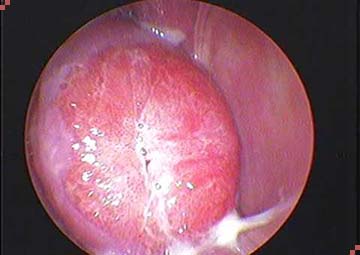

Khi đến phòng khám kiểm tra bằng máy sẽ thấy:

- Lớp biểu mô lẽ ra ở lỗ trong cổ tử cung, nhưng đã lan ra ngoài che phủ một phần cổ tử cung, ở dưới là lớp đệm.

- Có nhiều mạch máu tạo ra hình ảnh một tổn thương có màu đỏ và sần sùi giống như mô hạt.

Quan sát bằng máy sẽ thấy có 2 trường hợp bị viêm lộ tuyến cổ tử cung:

- Lộ tuyến nông là vùng tổn thương có thể xuất hiện trên diện rộng nhưng lớp tế bào liên kết ở bề mặt chưa hết hẳn.

- Lộ tuyến sâu là khi các lớp tế bào đã mất hết, lớp đệm phía dưới lộ hẳn lên bề mặt.

Mức độ viêm lộ tuyến cổ tử cung nặng hay nhẹ được đánh giá thông qua sự tổn thương của tế bào ở mức độ nông hay sâu. Để đánh giá chính xác mức độ tổn thương, cần phải khám và làm xét nghiệm tế bào.

Hình ảnh viêm lộ tuyến cổ tử cung